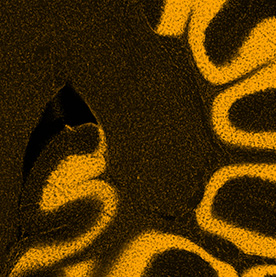

Individuals with autism experience and interact with the world differently than those without autism. Researchers use imaging methods to explore structural brain differences in humans with autism and in animal models to help identify signatures of the condition. Identifying such signatures may allow the development of improved diagnostics and treatments for autism patients.

This triptych shows three views of the folds of a mouse cerebellum, a part of the brain that helps control fine motion. In this form of artwork, the three panels create a story by highlighting a central figure with supporting imagery to either side. This triptych highlights the use of different stains for different features: yellow for the DNA inside brain cells, blue for support cells surrounding neurons. By layering multiple stains, researchers can understand how those elements interact in living tissues.